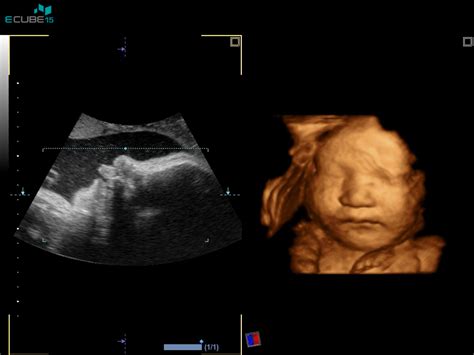

Nuhalna svetlina je v bistvu tekočina, ki se nabira v podkožju vratu ploda v prvem trimesečju nosečnosti. Ta zbir tekočine je na ultrazvočni sliki videti kot svetlejše območje v zatilju ploda. Njena prisotnost in debelina sta pomembna kazalnika, saj lahko povečana nuhalna svetlina nakazuje na večje tveganje za kromosomske nepravilnosti, kot so trisomija 21 (Downov sindrom), trisomija 18 (Edwardsov sindrom) in trisomija 13 (Patau sindrom). Poleg tega lahko povečana nuhalna svetlina nakazuje tudi na določene srčne napake ali druge strukturne nepravilnosti ploda, ki se sicer pogosto natančneje opredelijo šele v kasnejših obdobjih nosečnosti, običajno okoli 20. tedna.

Ultrazvočno merjenje nuhalne svetline je časovno zelo specifično. Opraviti ga je treba med 11. tednom nosečnosti (ko je dolžina ploda od vrha glavice do trtice, t.h. rastne dolžine ali CRL, približno 45 mm) in 13. tednom nosečnosti ter 6 dnevi (ko je dolžina ploda približno 84 mm). V tem obdobju je meritev najbolj zanesljiva. Izven tega časovnega okvira lahko natančnost meritve upade.

Da bi zagotovili natančno merjenje nuhalne svetline, je ključnega pomena, da je plod v ugodni legi za merjenje. Zaradi tega lahko sam pregled traja različno dolgo, odvisno od sodelovanja ploda. Med samim ultrazvočnim pregledom strokovnjak opravi več pomembnih meritev in ocen:

- Velikost ploda: Izmeri se dolžina ploda od vrha glavice do trtice (CRL), kar je ključno za določitev gestacijske starosti.

- Premer glavice: Ta meritev prav tako prispeva k oceni rasti in razvoja ploda.

- Prisotnost nosne kosti: Ocenjuje se prisotnost in razvoj nosne kosti v obraznem profilu ploda. Odsotnost ali slabo razvitost nosne kosti je pri 60 % plodov z Downovim sindromom, vendar se pojavi tudi pri 3 % normalnih nosečnosti. Ta podatek je pomemben dejavnik pri izračunu tveganja.